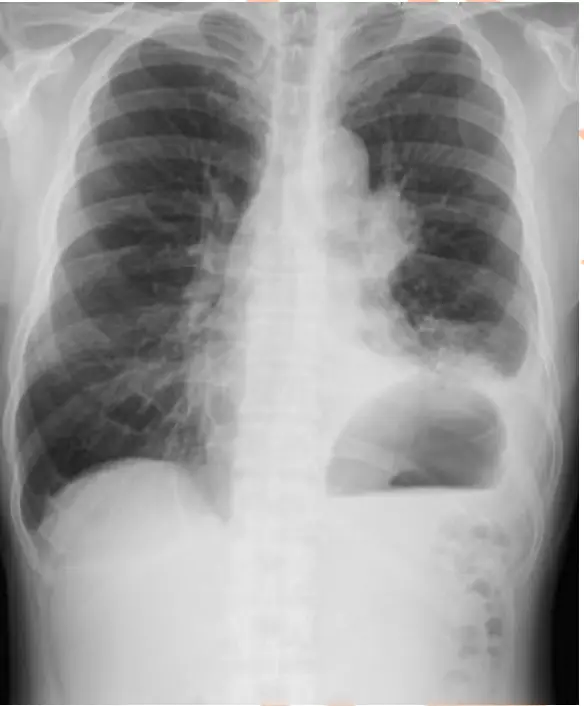

某位確診為肺癌病人,圖(七)為其胸部X光。表示病人的腫瘤有可能侵襲到某些神經並引發相關症狀,此病人最可能出現下列哪些症狀?

這張胸部X光顯示左側肺門(hilar)區有實質性腫瘤陰影,且左側膈肌高度明顯抬高,較右側明顯偏上。正常情況下,右側膈肌通常略高於左側,若左側膈肌反而抬高,應考慮左側膈肌運動受限或麻痺。此表現提示左側phrenic nerve(支配膈肌主要的運動神經)可能被腫瘤侵襲,導致左側膈肌功能喪失。

- 選項B 「活動時呼吸喘促」:phrenic nerve受損造成對側膈肌癱瘓,膈肌無法有效收縮,肺活量減少,特別在活動或平臥時會罹呼吸困難、運動誘發性呼吸喘促,與影像所示膈肌抬高吻合。